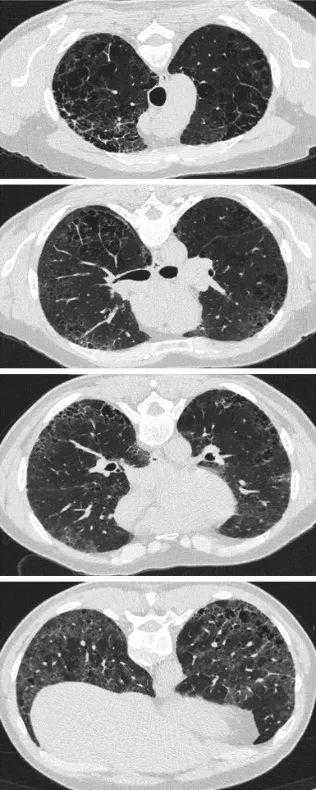

在IPF的背景下,HRCT上的磨砂玻璃样阴影主要代表细小的纤维化,CPFE的纤维化程度是通过将磨玻璃样阴影、网状和蜂窝囊肿加在一起来计算[118,171[。然而,纤维化程度的量化与体积损失相混淆,肺下叶有时严重收缩成很小纤维化区域。然而,当考虑CTD相关的ILD或fHP时,磨玻璃样阴影可能反映炎症而不是纤维化,对于磨玻璃样阴影是否应被视为CPFE纤维化程度的一部分,尚无共识。有人建议,为了符合CPFE定义所要求的“纤维化”因素,磨玻璃样阴影只有在被网状线或牵引性支气管扩张覆盖时才应被量化(图9和E4)[171]。就CPFE中ILD模式的量化达成一致,对于未来协调研究解释以及就首选的视觉纤维化量化方法(体积叶评分与五或六级HRCT切片评分;纤维化程度的分类与连续评分)达成一致将是重要的。

图9:肺气肿视觉评分。特发性肺纤维化和肺气肿患者上叶的轴向切面(上)。肺气肿通过肺叶不规则分布,使视觉量化困难。目视合并肺气肿病灶(下)并估计其组成的肺叶的比例(即,50%,33%,25%,20%,15%,10%或5%)可以简化复杂性病例的定量(见在线补充)。